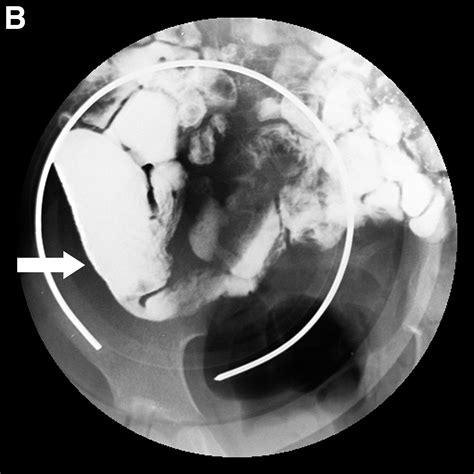

The Small Bowel Follow Through (SBFT) is a radiological examination that uses X-rays to visualize the small intestine. This procedure is particularly useful for detecting abnormalities such as strictures, obstructions, tumors, and inflammatory conditions like Crohn’s disease. The SBFT involves ingesting a barium solution, which coats the lining of the small intestine, making it visible on X-ray images.

• X-ray Imaging: As the barium solution moves through the small intestine, a series of X-ray images are taken at regular intervals. This allows the radiologist to observe the movement of the barium and identify any abnormalities.

Interpreting the results of an SBFT requires expertise in radiology. The radiologist will examine the X-ray images for any signs of abnormalities. Common findings include:

• Strictures: Narrowing of the intestinal lumen, which can be caused by inflammation, scarring, or tumors.

• Obstructions: Blockages that prevent the normal passage of intestinal contents.